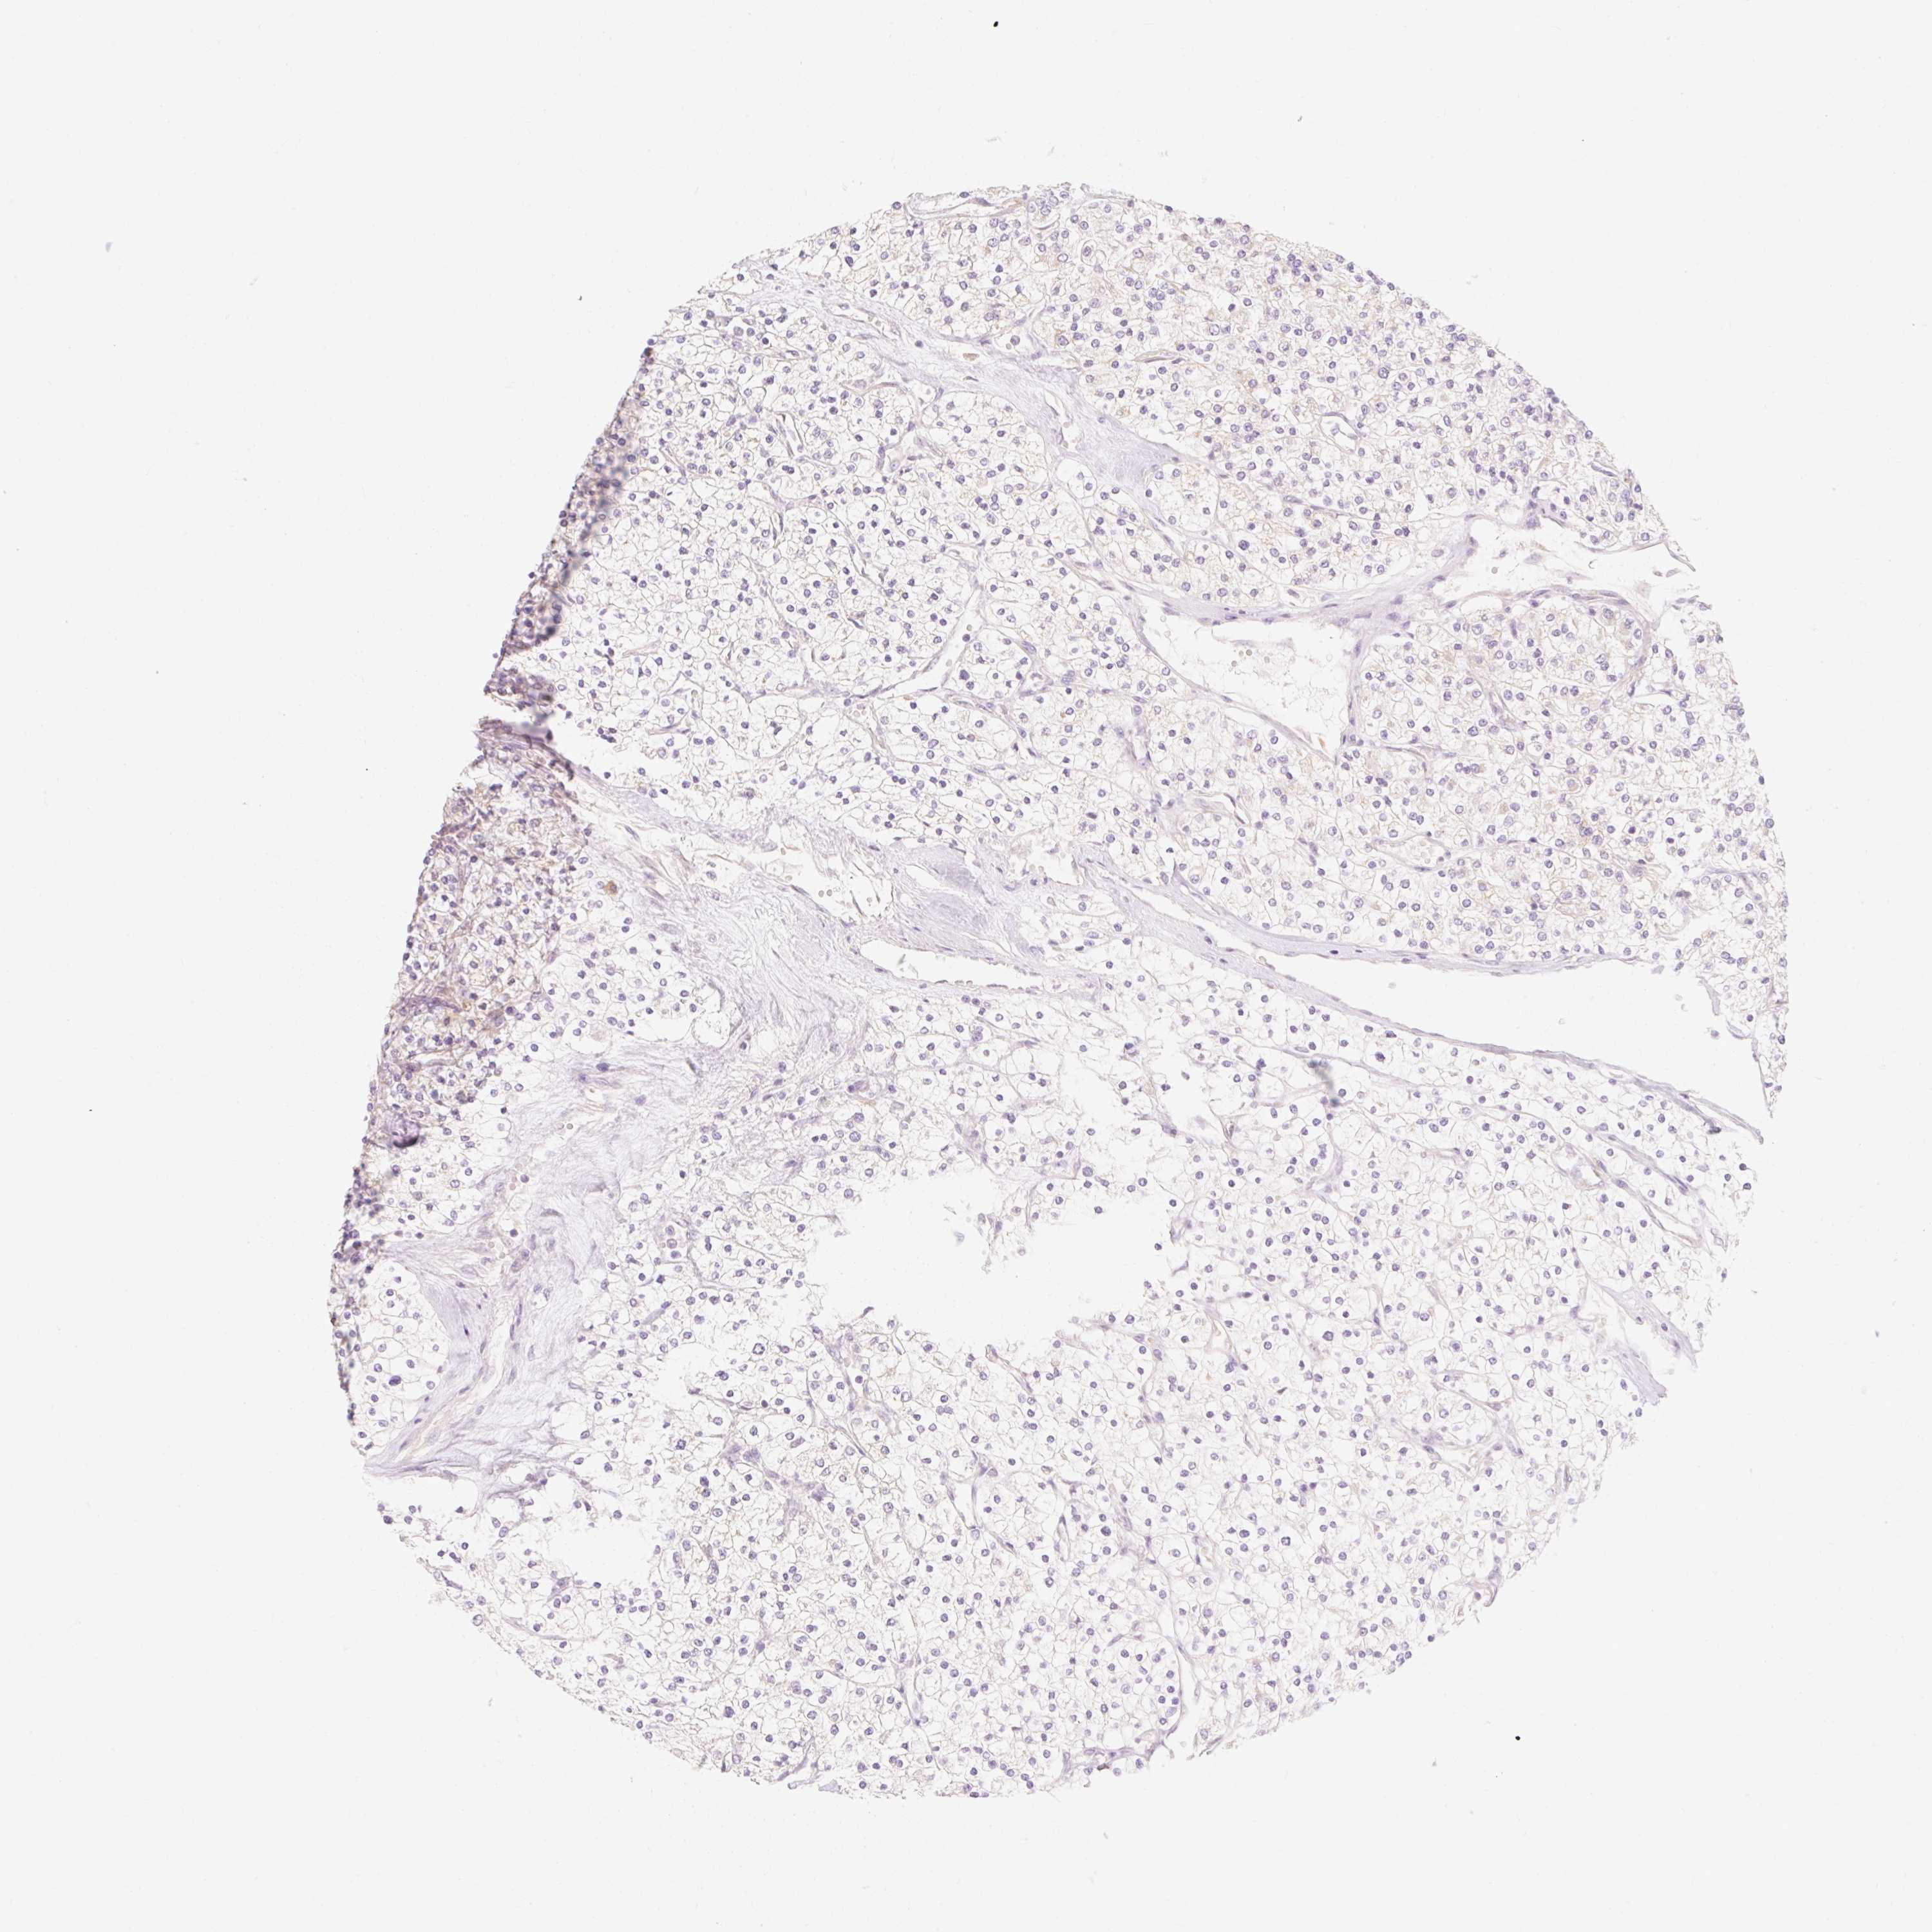

KIDNEY RENAL CLEAR CELL CARCINOMA (TCGA) - Interactive survival scatter ploti

The Survival Scatter plot shows the clinical status (i.e. dead or alive) for all individuals in the patient cohort, based on the same data that underlies the corresponding Kaplan-Meier plots. Patients that are alive at last time for follow-up are shown in blue and patients who have died during the study are shown in red.

The x-axis shows the expression levels (FPKM) of the investigated gene in the tumor tissue at the time of diagnosis. The y-axis shows the follow-up time after diagnosis (years). Both axes are complimented with kernel density curves demonstrating the data density over the axes. The top density plot shows the expression levels (FPKM) distribution among dead (red) and alive patients (blue). The right density plot shows the data density of the survived years of dead patients with high and low expression levels respectively, stratified using the cutoff indicated by the vertical dashed line through the Survival Scatter plot. This cutoff is automatically defined based on the FPKM cutoff that minimizes the p-score. The cutoff can be changed by dragging the vertical line or by entering a cutoff value in the square labeled "Current cut-off".

Under the Survival Scatter plot the p-score landscape (black curve; left axis) is shown together with dead median separation (red curve; right axis). Dead median separation is the difference in median mRNA expression between patients who have died with high and low expression, respectively. It is calculated as follows: median FPKM expression of dead patients with high expression - median FPKM expression of dead patients with low expression. This is intended to aid the user in visually exploring custom cutoffs and the associated p-scores and dead median separation.

Individual patient data is displayed and can be filtered by clicking on one or more of the category buttons on the top of the page. Categories describing expression level and patient information include: high, low, alive, dead, female, male and tumor stages. The scale of the x-axis can be toggled between linear and log-scale by clicking on the "x log" button. Mouse-over function shows TCGA ID, patient information and mRNA expression (FPKM) for each patient.

& Survival analysisi

Kaplan-Meier plots summarize results from analysis of correlation between mRNA expression level and patient survival. Patients were divided based on level of expression into one of the two groups "low" (under cut off) or "high" (over cut off). X-axis shows time for survival (years) and y-axis shows the probability of survival, where 1.0 corresponds to 100 percent.

MYO1D is potential prognostic, high expression is favorable in Kidney Renal Clear Cell Carcinoma (TCGA)

: 13.05

Average pTPM 23.7

Number of samples 521